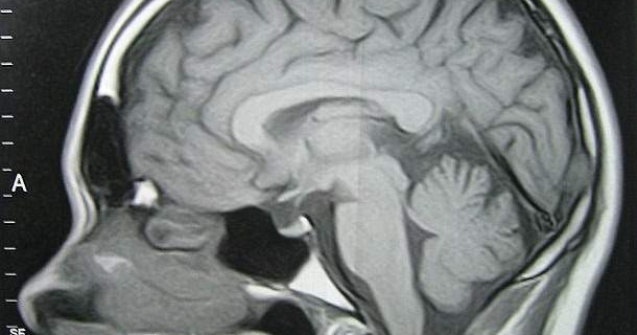

Fostul dinamovist Cosmin Pascovici, a aflat, in 2006, ca fiul sau are o tumoare la creier. Desi copilul s-a vindecat, tratamentul costa 4000 de lei, lunar.

Soc. Denis Mircea Mihail, care ieri a implinit 2 ani, a fost operat de tumora la creier la Spitalul Bagdasar-Arseni, jucatorul pierzand derby-ul cu Steaua